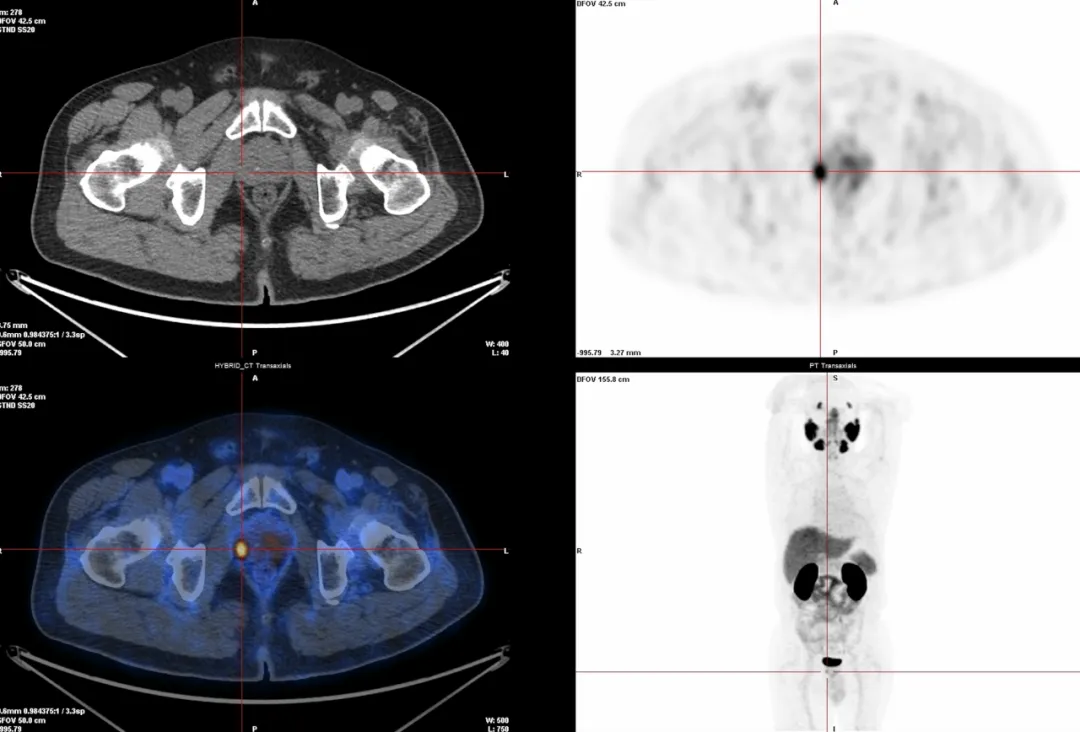

△前列腺癌微小原发灶检测